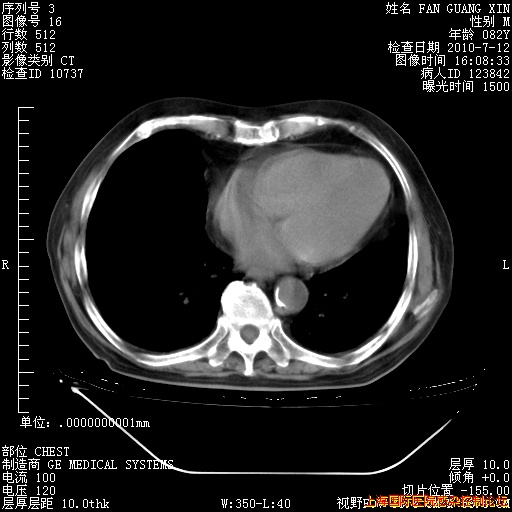

6月12日纵膈窗

今天复查CT

整整相隔30天的肺部CT好像有所好转啊。甲强龙减量第3天,需要观察体温。

海管,自昨日你和我通完话后,不知您岳父消化道症状有无缓解?体温怎样?阅读7.12日胸部ct,个人认为目前激素治疗是有效的,甲强龙减量是适宜的。因在抗痨治疗,需密切观察肝功、肾功能和血常规。不过,老年、长期住院和大量使用激素,很担心菌群失调发生